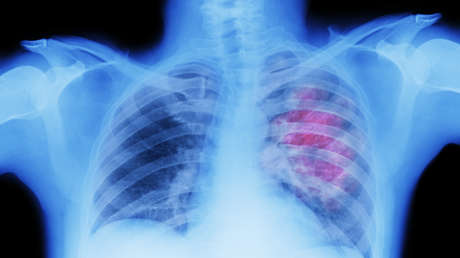

El linfoma no Hodgkin es un tipo se cáncer que se origina en los glóbulos blancos y afecta el sistema linfático, que forma parte del sistema inmunitario del cuerpo, detalla la Sociedad Americana contra el Cáncer.

Esta enfermedad es más común entre las personas mayores de 60 años. Según su extensión y el subtipo del cáncer, la tasa de supervivencia a 5 años varía del 64 % al 84 %informa la Sociedad Americana de Oncología Clínica.